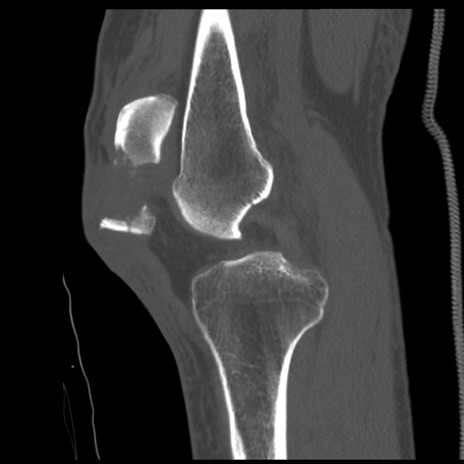

症例28 右膝関節CT(矢状断像)

右膝関節CT